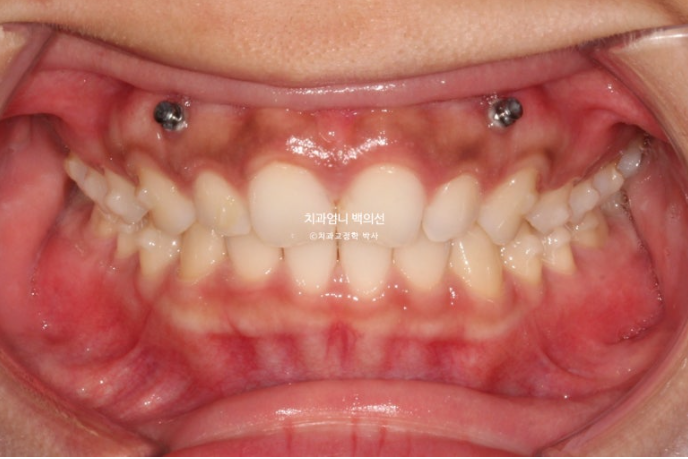

앞니를 위로 좀더 올려 거미스마일을 더 개선하고자 추가장치를 제작했습니다.

중간에 잇몸성형도 했습니다. 치아를 과도하게 덮고 있는 잇몸을 걷어내는 과정입니다.

24년 9월부터 25년 1월까지, 5개월간 14개 추가장치를 모두 낀 후 모습입니다.

총 치료기간은 10개월 입니다.

25.01

길이가 짧아 답답해보이던 앞니가 잇몸성형으로 비율이 좋아지며 보기에 시원해졌습니다.

좋았던 교합은 잘 유지되었고

24.03~25.01

좋아진 배열과 사라진 틈.

이제 전후 비교 보겠습니다.

과개교합의 확실한 개선